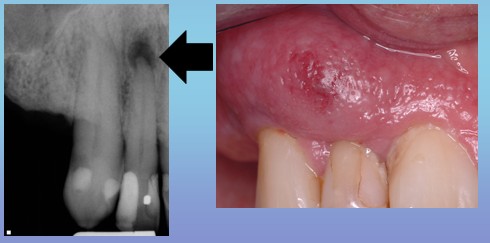

牙 如果任由疾病的发展,牙髓腔内的炎性物质无法顺利排出,就会通过根尖处的小孔挤进牙根尖周围,引起根尖周围发炎,简称“根尖周炎”。越来越多的渗出物在根尖处聚集,压力不断增大,患者在感受疼痛的同时,也会觉得牙齿有“伸长感”。

齿 好可怕!听说过,有了“伸长感”都不敢闭嘴,似乎一闭嘴别的牙没碰到,就先碰到这个牙齿了。那该如何治疗呢?

牙 医生多会在牙齿的表面磨个洞,使里面的过大的“压力”释放出来,疼痛就会得到明显的缓解。对了齿哥,你听说过有坐飞机牙痛的吗?